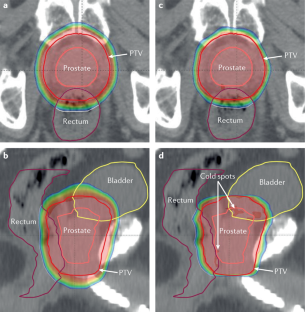

Heemsbergen, W. D. et al. Increased risk of biochemical and clinical failure for prostate patients with a large rectum at radiotherapy planning: results from the Dutch trial of 68 GY versus 78 Gy. Int. J. Radiat. Oncol. Biol. Phys. 67, 1418–1424 (2007).

De Crevoisier, R. et al. Increased risk of biochemical and local failure in patients with distended rectum on the planning CT for prostate cancer radiotherapy. Int. J. Radiat. Oncol. Biol. Phys. 62, 965–973 (2005).

Moiseenko, V., Liu, M., Kristensen, S., Gelowitz, G. & Berthelet, E. Effect of bladder filling on doses to prostate and organs at risk: a treatment planning study. J. Appl. Clin. Med. Phys. 8, 55–68 (2006).